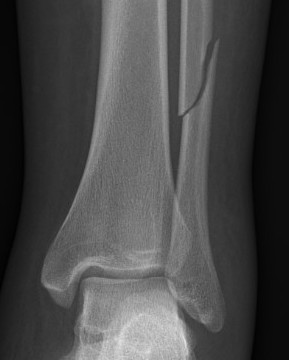

Xray

Ankle fractures with deltoid ligament rupture / Bimalleolar equivalent injury

Maisonneuve injury with proximal fibular fracture and increased medial clear space

Weber B with increased medial clear space on CT

Weber C with increased medial clear space